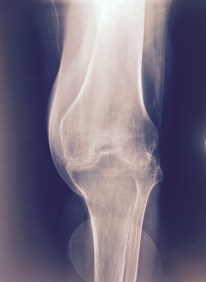

The commonest clinical presentation of knee pain in my practice in patients above the age of 60 is osteoarthritis. This disease continuous progression is almost assured. Despite a few cases, most symptomatic osteoarthritis of knee progressively worsens over time especially patient with a obvious shortening and antalgic(Painful) gait.The common gait abnormality of gait exprienced among my patients is antalgic with varus thrust (as seen picture below) with obvious bowing of knees. This patient who usually be using a walking aid and be taking a variety of painkillers (prescribed or otherwise) for numerous years and now wishes to seek a permanent solution to the problem.